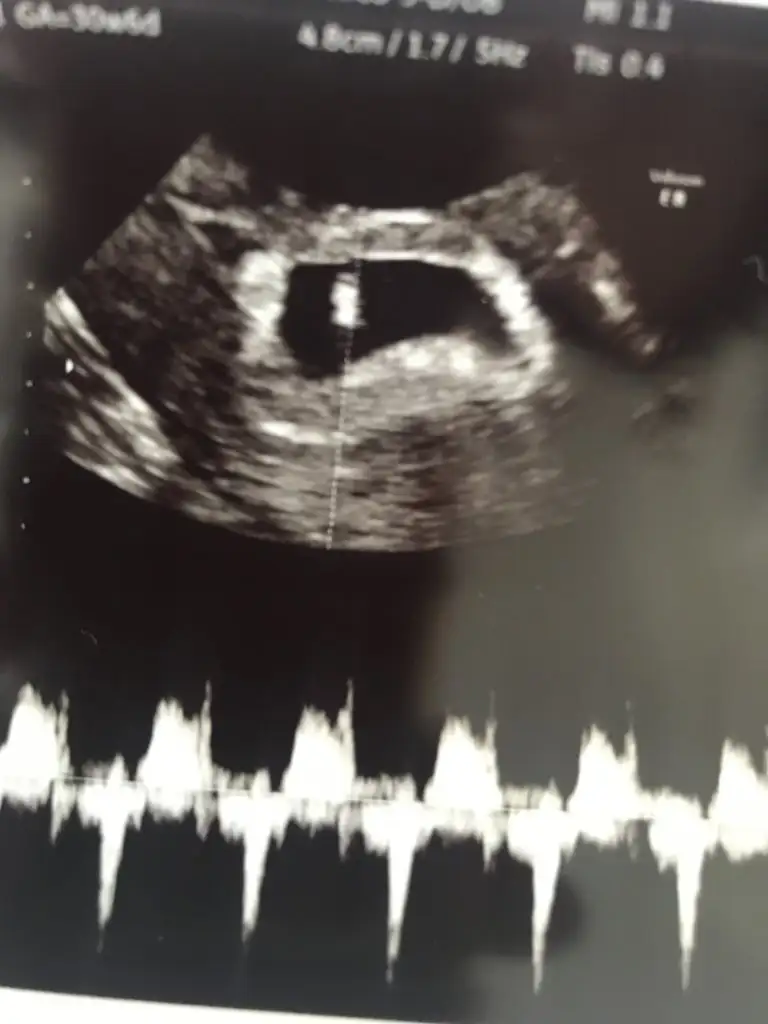

11+2 de olan görüntümüz karından bakıldı bana da bi tahminde bulunur musunuz🥰

• 20220314_101614.webp

20220314_101614.webp

31,2 KB · Görüntüleme: 3.364